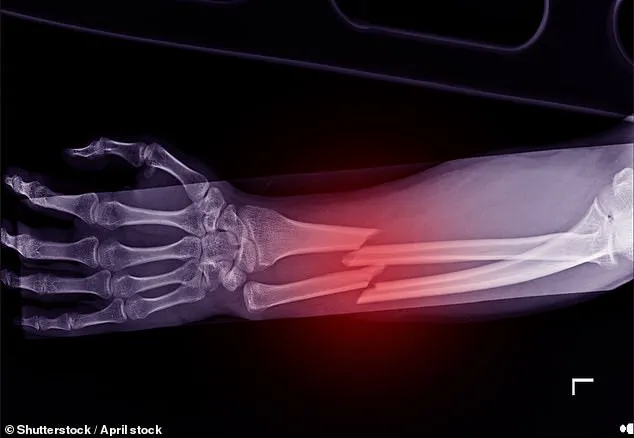

Osteoporosis, a condition that weakens bones and increases the risk of fractures, affects 3.5 million people in the UK.

Alarmingly, one in two women over the age of 50 will experience a bone break due to the disease.

These medications significantly reduce the likelihood of life-threatening hip fractures, which are among the most severe complications of the disease.

According to the National Institute for Health and Clinical Excellence (NICE), more than a quarter of hip fracture patients die within a year of their injury, with one in ten dying within a month.